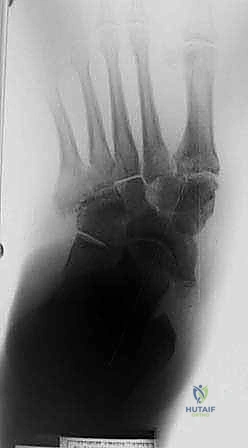

لفهم أهمية التثبيت الجراحي، يجب أولاً أن نفهم طبيعة المرض المدمر الذي نواجهه. قدم شاركو هي حالة مرضية خطيرة تصيب العظام والمفاصل والأنسجة الرخوة في القدم والكاحل. تحدث هذه الحالة بشكل رئيسي لدى المرضى الذين يعانون من الاعتلال العصبي المحيطي (Peripheral Neuropathy)، وهو فقدان الإحساس في الأطراف السفلية نتيجة ارتفاع مستويات السكر في الدم لفترات طويلة.

عندما يفقد المريض الإحساس بالألم والحرارة في قدميه، فإنه يستمر في المشي والضغط على مفاصل القدم رغم وجود إصابات دقيقة أو كسور شعرية غير ملحوظة. ومع استمرار الضغط الميكانيكي، تبدأ عظام القدم في التفتت والانهيار.

- الانهيار الهيكلي: تنهار عظام منتصف القدم، مما يؤدي إلى سقوط قوس القدم الطبيعي وتحول أسفل القدم إلى شكل محدب يشبه "الكرسي الهزاز" (Rocker-bottom deformity).

| المرحلة 1 | التفتت والانهيار (Fragmentation) | تدمير نشط للمفصل، كسور متعددة، خلع في المفاصل، تورم شديد وحرارة. | استمرار منع التحميل، الجبس المتصل (TCC). |